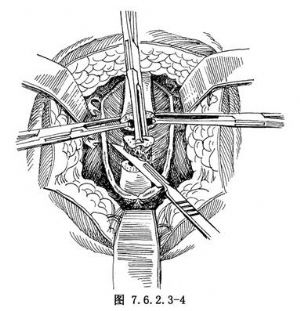

3.切除瘢痕狹窄段尿道 經尿道外口插入一尿道探子,其尖端受阻部位即爲尿道狹窄的遠端。於探子尖端受阻處的正常尿道上橫行切斷,遠側尿道斷端用組織鉗全層夾住以暫時止血,再切除瘢痕狹窄的尿道段,顯露出正常的近側尿道斷端,斷端亦用組織鉗全層鉗夾提起(圖7.6.2.3-4)。